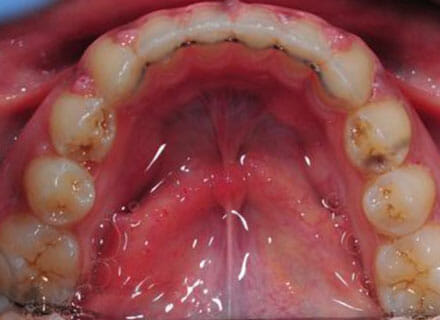

Open bite, protruding upper teeth

How a big open bite can be closed down while at the same time straightening all the teeth and closing gaps! Using clear fixed braces over around 18 months. Please note that the swollen gums in the after photos are what happens if a patient is not cleaning carefully enough or seeing the hygienist during treatment – after careful cleaning and hygiene treatment these gums returned to normal!